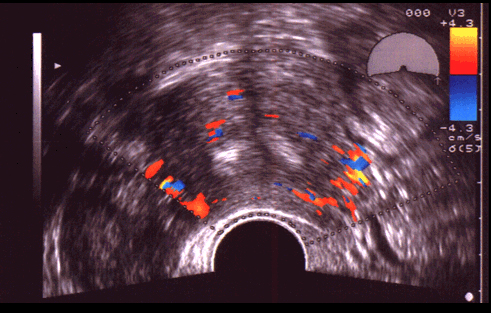

Malformation utérine. L'utilisation du doppler couleur aide à la définition d'un utérus cloisonné par la présence d'une vascularisation concentrique avec un septum peu vascularisé.